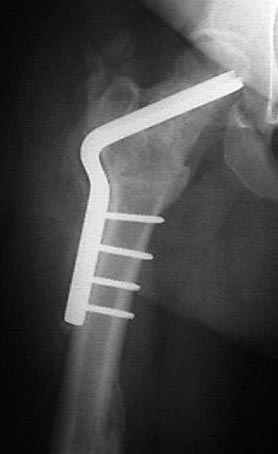

Если, например, доводится лечить больных с псевдартрозами шейки бедра, то надобность есть, и приходится. См. приложение.

Несколько снимков из моей коллекции, чтобы разьяснить, почему мы до сих пор делаем различные варианты остеотомии.

На рисунке N1 предоперационный план лечения ложного сустава шейки бедра- линия ложного сустава, угол и направление введения импланта, клиновидная остеотомия в градусах и миллиметрах, второй снимок после коррекции, расчет, на сколько удлиняется конечность и размеры импланта;

N3 рисунок окончательный снимок, после операции моя рентгенограмма должен выглядеть примерно как эта картина. На N4 снимке клин перед удалением; N5 послеоперации 3 нед.; N6 окончательная рентгенограмма.

варус при проксимальном отделе 95 градусной пластиной.